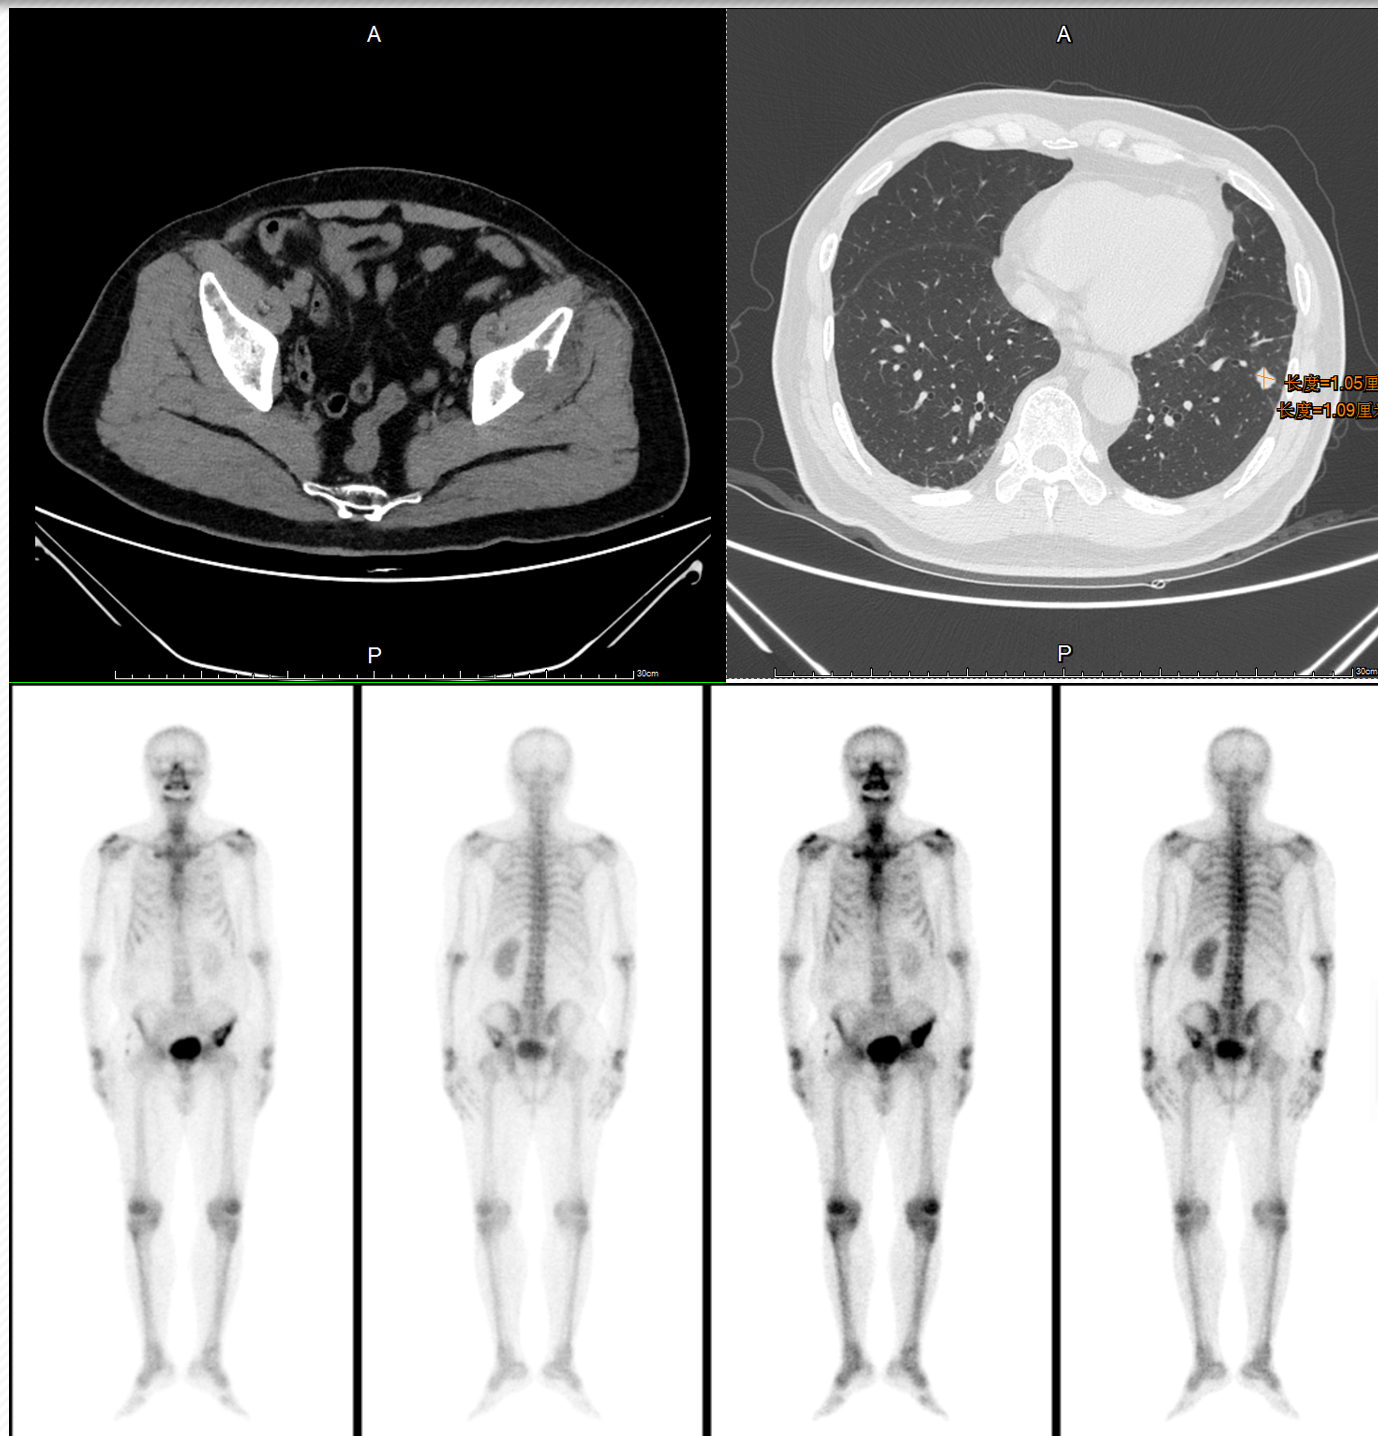

• 2024.01复查肺CT:双肺肺内可见多处小结节影,大者直径约为11mm,考虑转移瘤可能。余脑/骨/全腹盆腔未见明确复发转移

• 确诊右肾透明细胞癌并双肺多发转移(T2aN0M1 IV期)。IMDC及MSKCC预后评分:2分(初始至开始系统性治疗时间<1年/贫血)、中危。

• 2024.01予以“培唑帕尼200mg qd”靶向治疗;2024.03加量至“培唑帕尼400mg qd”靶向治疗

• 2024.3、2024.6复查:双肺肺内可见多处小结节影,部分缩小,部分结节内空洞形成。

• 2024.10复查疾病进展并出现骨转移,考虑患者不规则用药,予重新恢复口服培唑帕尼,并加量至600mg qd。

• 2024.12培唑帕尼加量至800mg qd,监测血压波动在125-156/81-101mmHg间,每日解2-3次稀糊样便,药物控制不佳,改“培唑帕尼800mg qd”维持至今,期间疗效评价SD,未见颅内转移。